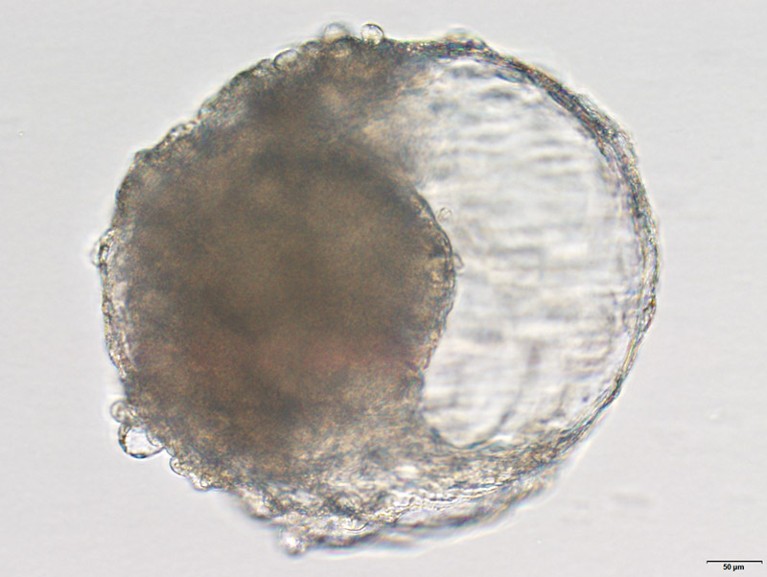

由食蟹猴干細胞生成的胚細胞。胚泡類似于胚胎的早期階段,并在植入猴子子宮時引發類似懷孕的變化。

上海中國科學院神經科學研究所的發育生物學家Zhen Liu和他的同事們轉向食蟹猴(Macaca fascicularis),它們通常被用作實驗動物,因為它們與人類在生物學上有一些相似之處。在細胞培養中,研究人員將猴子胚胎干細胞暴露于各種生長因子中,使它們分化成天然囊胚中的細胞類型。大約一周后,干細胞形成了囊胚的標志性球形結構,并分化成為組織和器官形成奠定基礎的三種細胞系。作者說:“這甚至在自然猴囊胚的體外長時間培養研究中都沒有實現。”